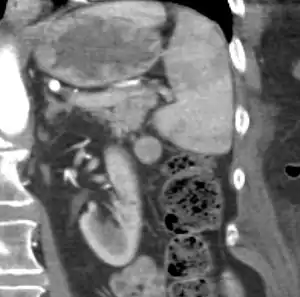

| CT scan of an accessory spleen (circular object in center of image) between the spleen and left kidney. | |